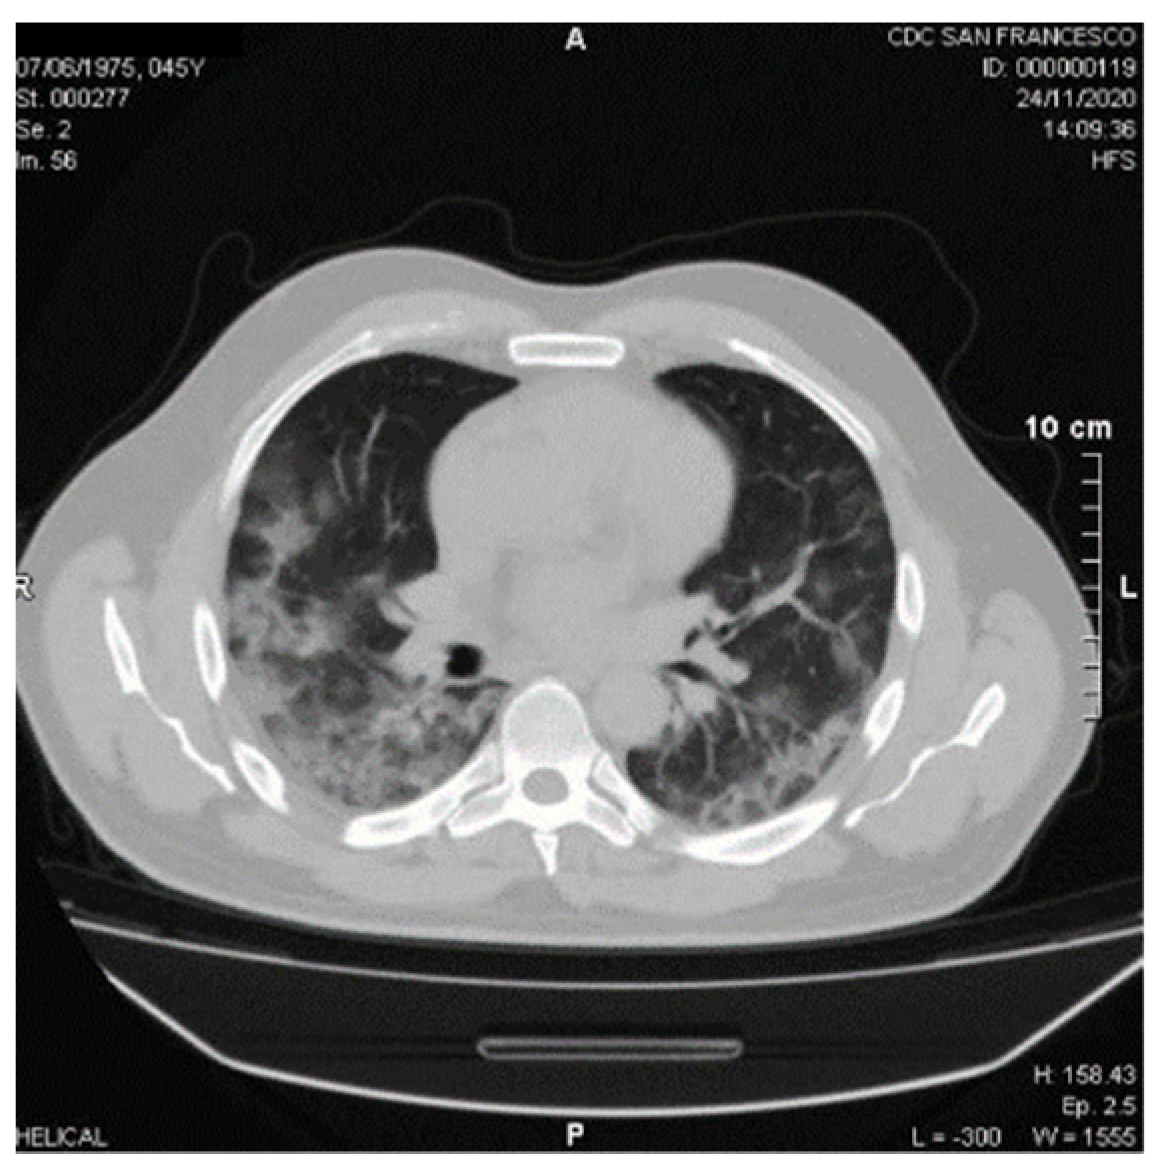

4. Potential Benefits of DOACs in COVID-19

5. Clinical Case